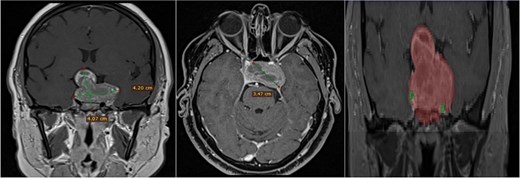

A 42-year-old male patient presented with a history of difficulty seeing in both temporal fields. The examination confirmed said bitemporal hemianopsia. We observed a sellar lesion in the MRI (T1, T2, and T1 sequences with contrast). With the segmentation, we were able to almost reconstruct the cavernous sinus and the internal carotid artery wholly in its intracavernous and clinoid portion and thus take more caution in the most rostral and dorsal region of the tumor since it was the site where both clinoid carotid arteries were closest each other (Fig. 7).

MRI and 3D volumetric segmentation of pituitary macroadenoma. Note the proximity of the internal carotid artery (green) in the most rostral and dorsal region of the tumor (red). Cavernous sinus (blue).